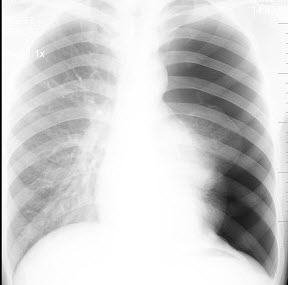

24、单项选择题

男,22岁,感胸痛且大汗淋漓就诊,X线检查如图,最可能的诊断是()